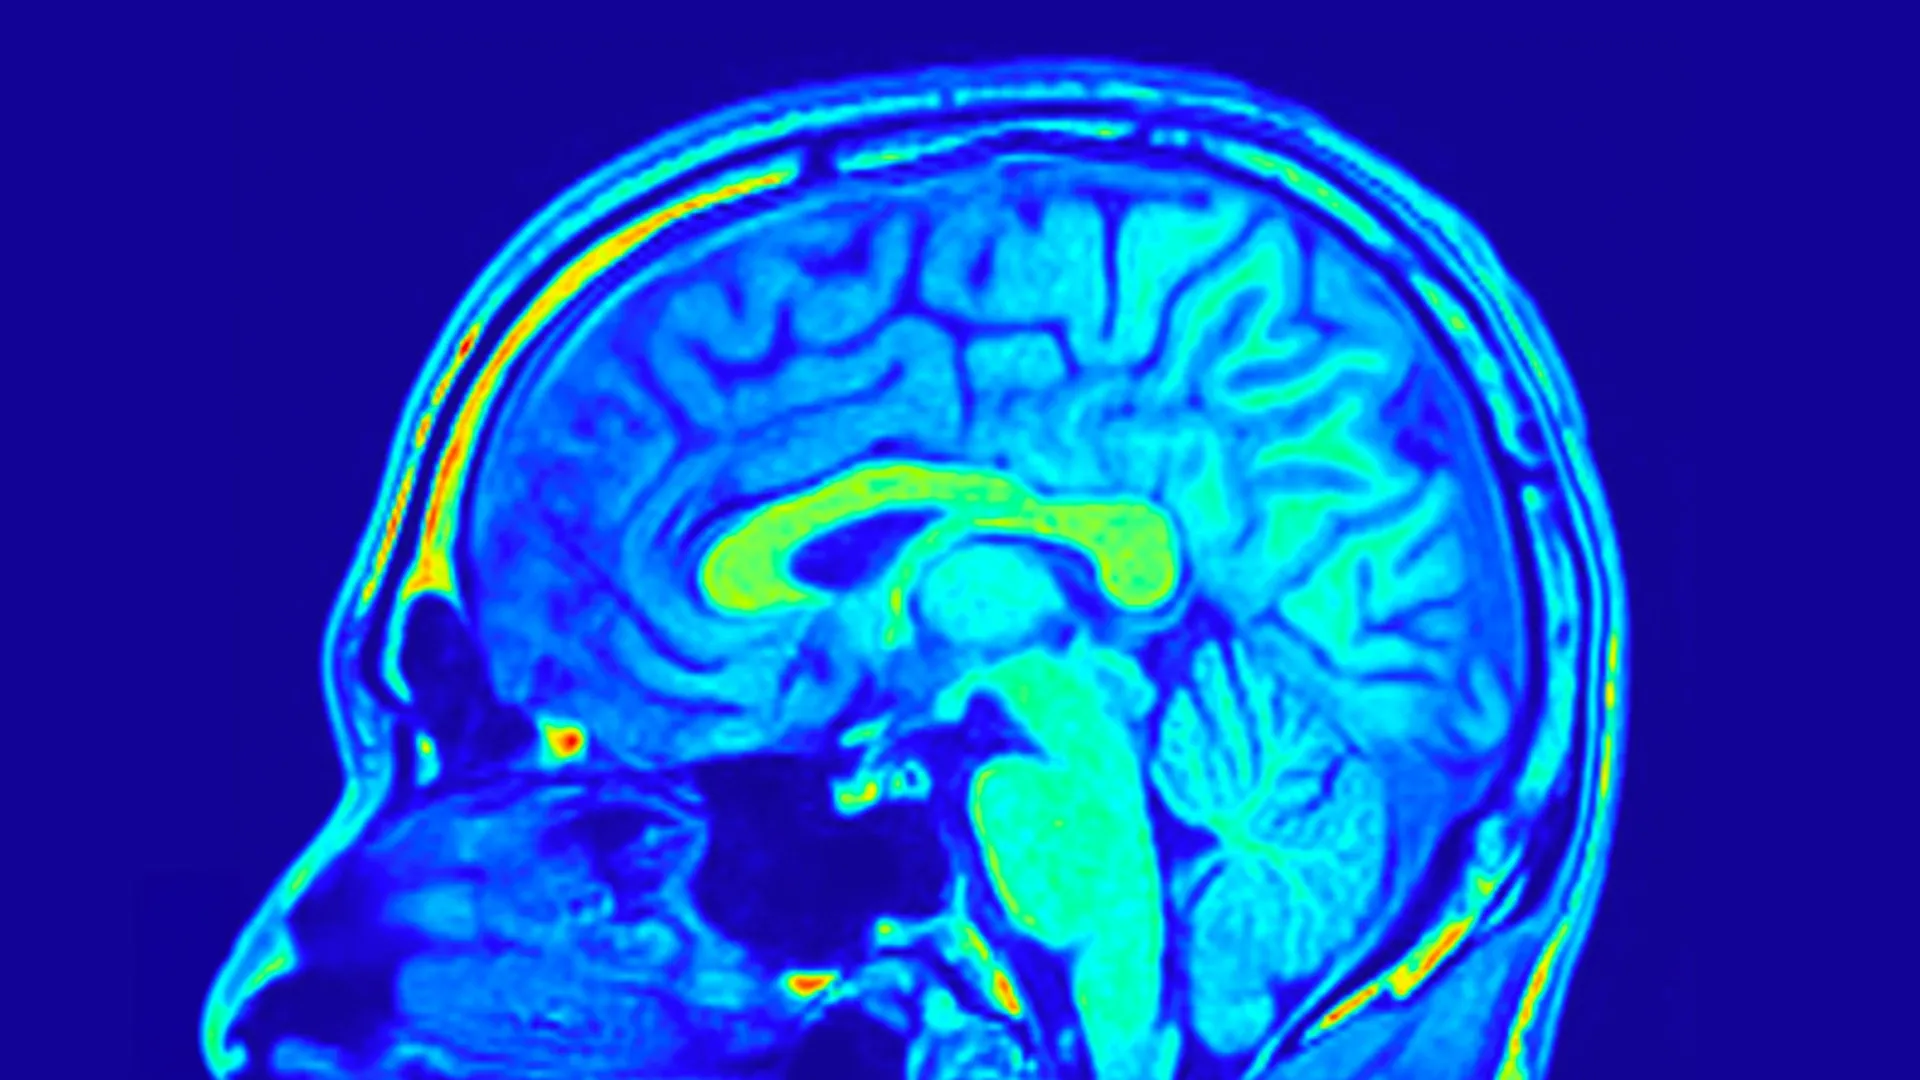

#BrainResearch #CognitiveScience #Neuroscience